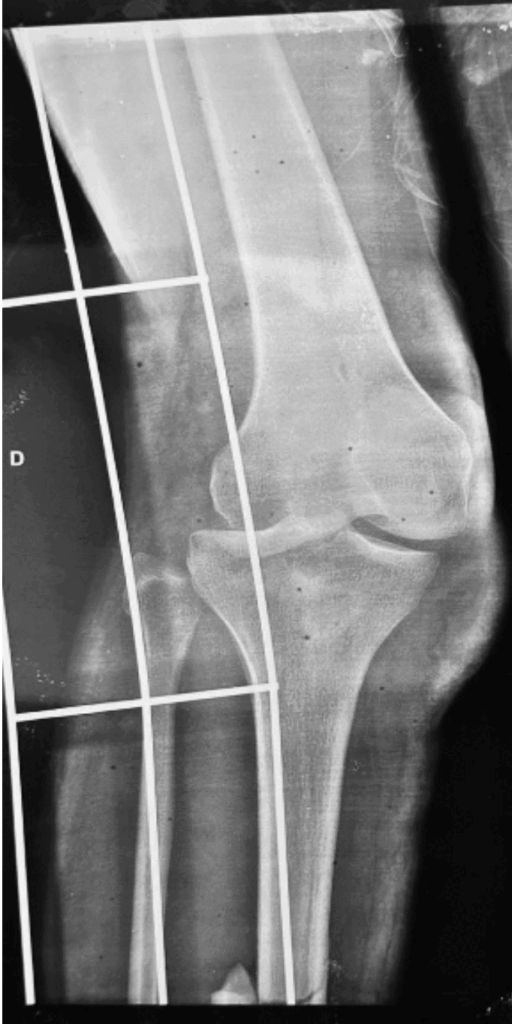

Paciente masculino de 20 anos, natural da Colômbia e residente em Porto Velho, Rondônia, sofreu uma colisão entre motocicleta e automóvel, sendo arremessado contra um muro. Na admissão, cinco horas após o acidente, radiografias revelaram luxação coxo-femoral posterior direita, luxação posterior de joelho direito (Figura 1), fratura do anel pélvico (Figura 2) e fratura diafisária da tíbia direita (Figura 3), além de lesão neurológica no membro inferior, sem comprometimento vascular.

Figura 1 – Radiografia do Joelho Direito

Descrição: Radiografias iniciais em pronto socorro do joelho direito em incidências AP e oblíquo com a presença de artefato (tala flexível de imobilização), visualizando uma sobreposição do côndilo lateral do fêmur sobre o planalto tibial, com perda da congruência articular. Nota-se a posteriorização da tíbia com desvio lateral em relação ao eixo femoral, sendo compatível com luxação posterior da tíbia. Além desses achados, constata-se uma solução de continuidade em terço médio da tíbia.

Fonte: Banco de dados do Hospital de Base Dr. Ary Pinheiro – HBAP.